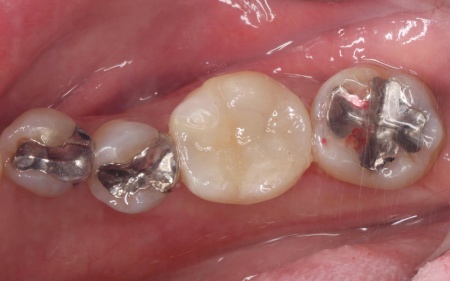

治療前

治療中

治療後

| 診断 | 拝見したところ、左下奥歯にプラスチックの詰め物であるコンポジットレジンが詰められていましたが、隣り合う歯との間が欠けている状態でした。

このまま放置すると、欠けた隙間から細菌が入り込んで虫歯が再発するおそれがあります。 |

| 行ったご提案・治療内容 | 患者様は「審美性が高く、丈夫な素材で修復したい」と希望されています。 そこで、新しい詰め物の形状はより強度を高めるため、噛む力を覆うように広範囲を修復する「アンレー」を用いることを提案し、同意いただきました。 また、詰め物の素材には「セラミック」の一種である「E-MAX(イーマックス)」を採用しています。 E-MAXのメリット E-MAXのデメリット まずは古いコンポジットレジンを除去し、アンレーを装着するために歯の形を整えます。 その後、型取りを行い、仮詰めをして初回の治療を終了しています。 後日、完成したE-MAXアンレーを装着し、歯にぴったりと合っているか、噛み合わせに問題がないかを確認して、治療を終了しました。 |